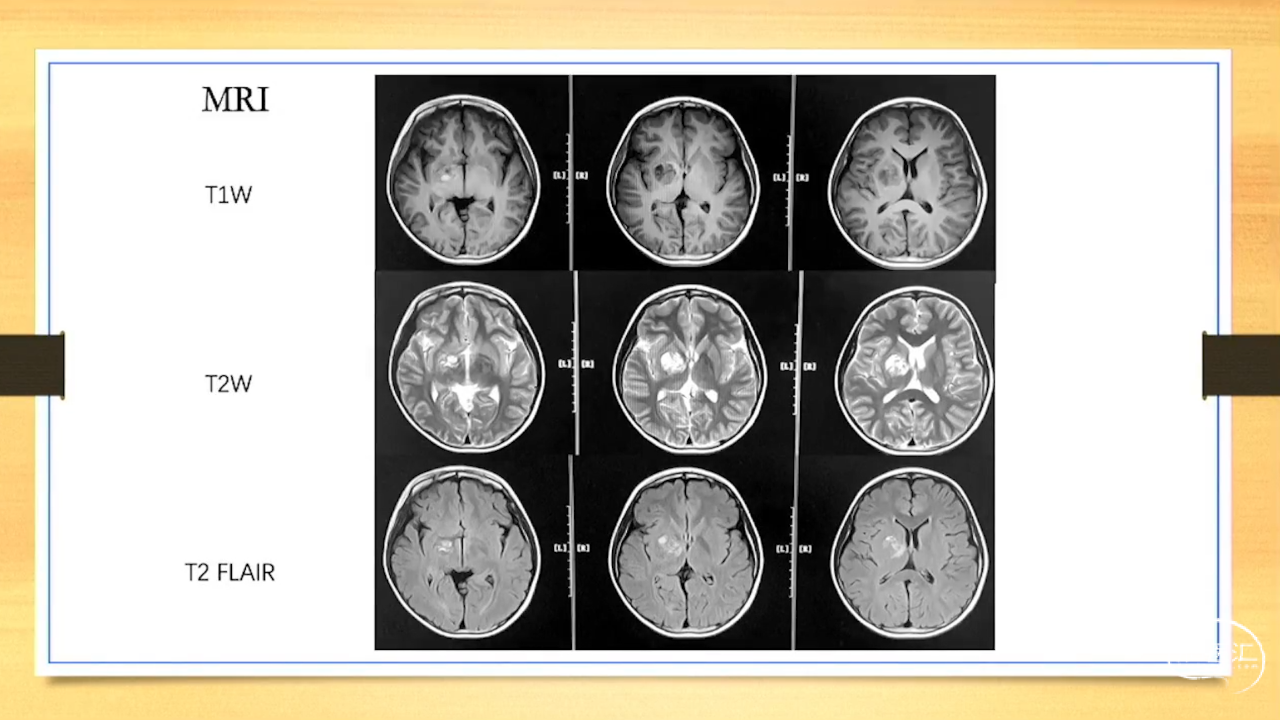

张荣教授:儿童颅内生殖细胞瘤的手术治疗

颅内生殖细胞肿瘤的治疗是手术、放疗、化疗、内分泌及其他多学科的整合治疗。及时、精准、合理的手术治疗是iGCT患者提高生存率、降低并发症、改善神经内分泌功能的关键。